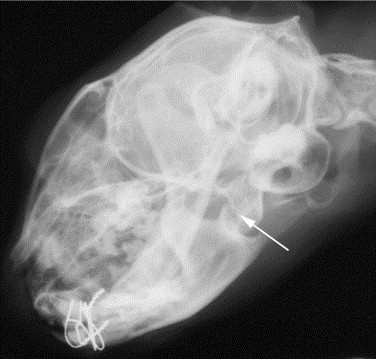

Peripheral vestibular signs may follow any trauma to the head, secondary to a fracture of the petrosal part of the temporal bone or tympanic bulla.10 This often is accompanied by facial paresis/paralysis. Skull radiography or advanced imaging will be necessary for an accurate diagnosis (Figure 56-20 ). Treatment is supportive and should be focused on any concurrent injuries sustained during the trauma.

Figure 56-20.

A lateral oblique radiograph of a 9-year-old cat with severe head trauma and peripheral vestibular syndrome after being hit by a car. No evident trauma was identified in the bullae, but the severity of the trauma to this area of the head can be estimated from the nearby fracture of the temporomandibular condyle (arrow).